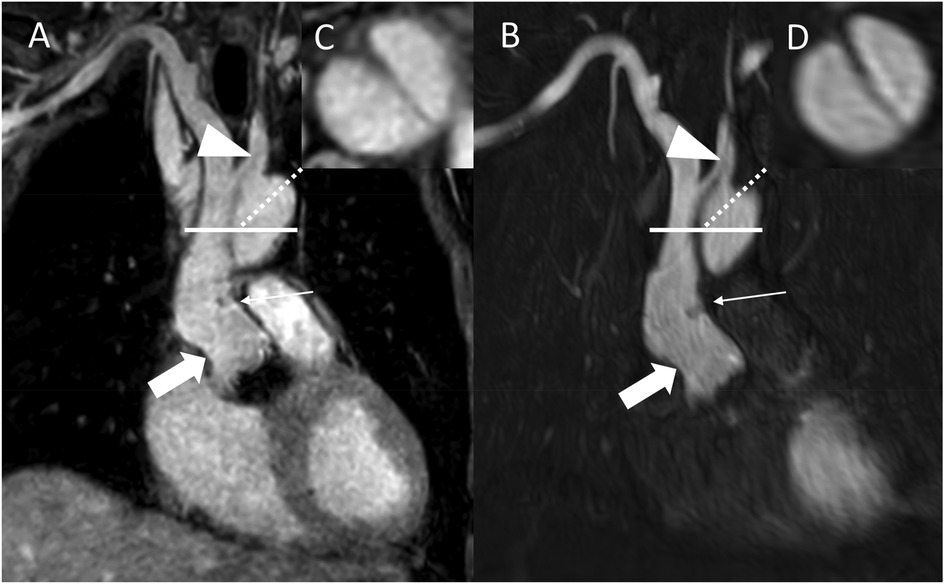

REACT [(A), source images, water-only, coronal plane] and CE-MRA [(B), source images, coronal plane] in a 54-year-old male after bentall procedure due to Stanford type A aortic dissection (AD). The delineation of the aortic graft (wide arrow: mid graft, thin arrow: distal anastomosis) and remaining AD affecting the aortic arch and the left common carotid artery (arrowhead) is comparable in both sequences. The axial reformation [square; REACT: (C) CE-MRA: (D)] serves to highlight the delineation of the dissection membrane in both sequences. CE-MRA, contrast-enhanced magnetic resonance angiography; REACT, relaxation-enhanced angiography without contrast and triggering.

Figure 5

REACT [source images, water-only, coronal (A) and parasagittal planes (C)] and CE-MRA [source images, coronal (B) and parasagittal planes (D)] in a 27-year-old male after Bentall procedure due to Stanford type A aortic dissection. Note the superior delineation of the aortic graft (wide arrow: mid graft) and the left coronary artery (arrowhead) in REACT due to motion artifacts in CE-MRA. While the distal anastomosis and suture lines can be delineated in both sequences (thin arrows), REACT yields a superior delineation of these structures due to above mentioned artifacts in CE-MRA. CE-MRA, contrast-enhanced magnetic resonance angiography; REACT, relaxation-enhanced angiography without contrast and triggering.

Figure 6